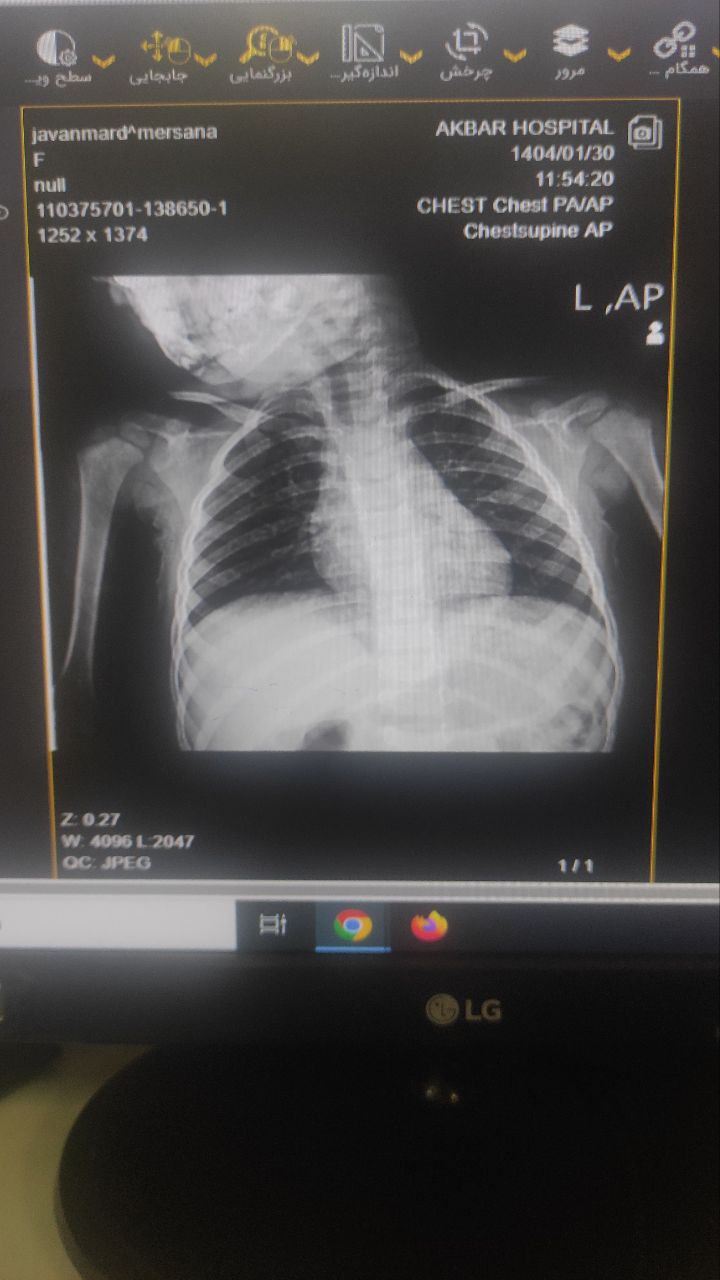

X-Ray: